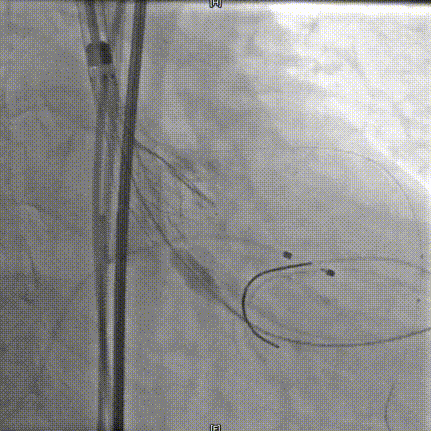

20mm球囊预扩

术中20mm球囊预扩可见轻微腰征,轻微瓣周漏,左冠充盈速度减慢,为保证患者安全,决定行冠脉保护,预防冠脉阻挡风险。选择AV26瓣膜,TaurusElite AV26瓣膜送至主动脉弓,输送系统轻松过弓及跨瓣,精准定位无冠窦最低点。

TaurusElite AV26瓣膜第一次释放定位位置接近瓣环,李怡教授准确定位判断,零位释放,瓣膜在手术计划的位置牢牢站稳了!手术过程行云流水,团队配合默契,操作细致熟练,主动脉根部造影及食道超声均只有少量瓣周漏;压差由术前的100mmHg直线下降到术后的5mmHg以内,TaurusElite首秀成功!